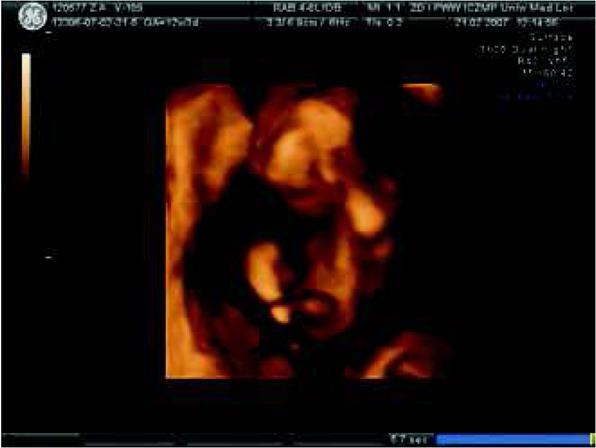

Fig. 1